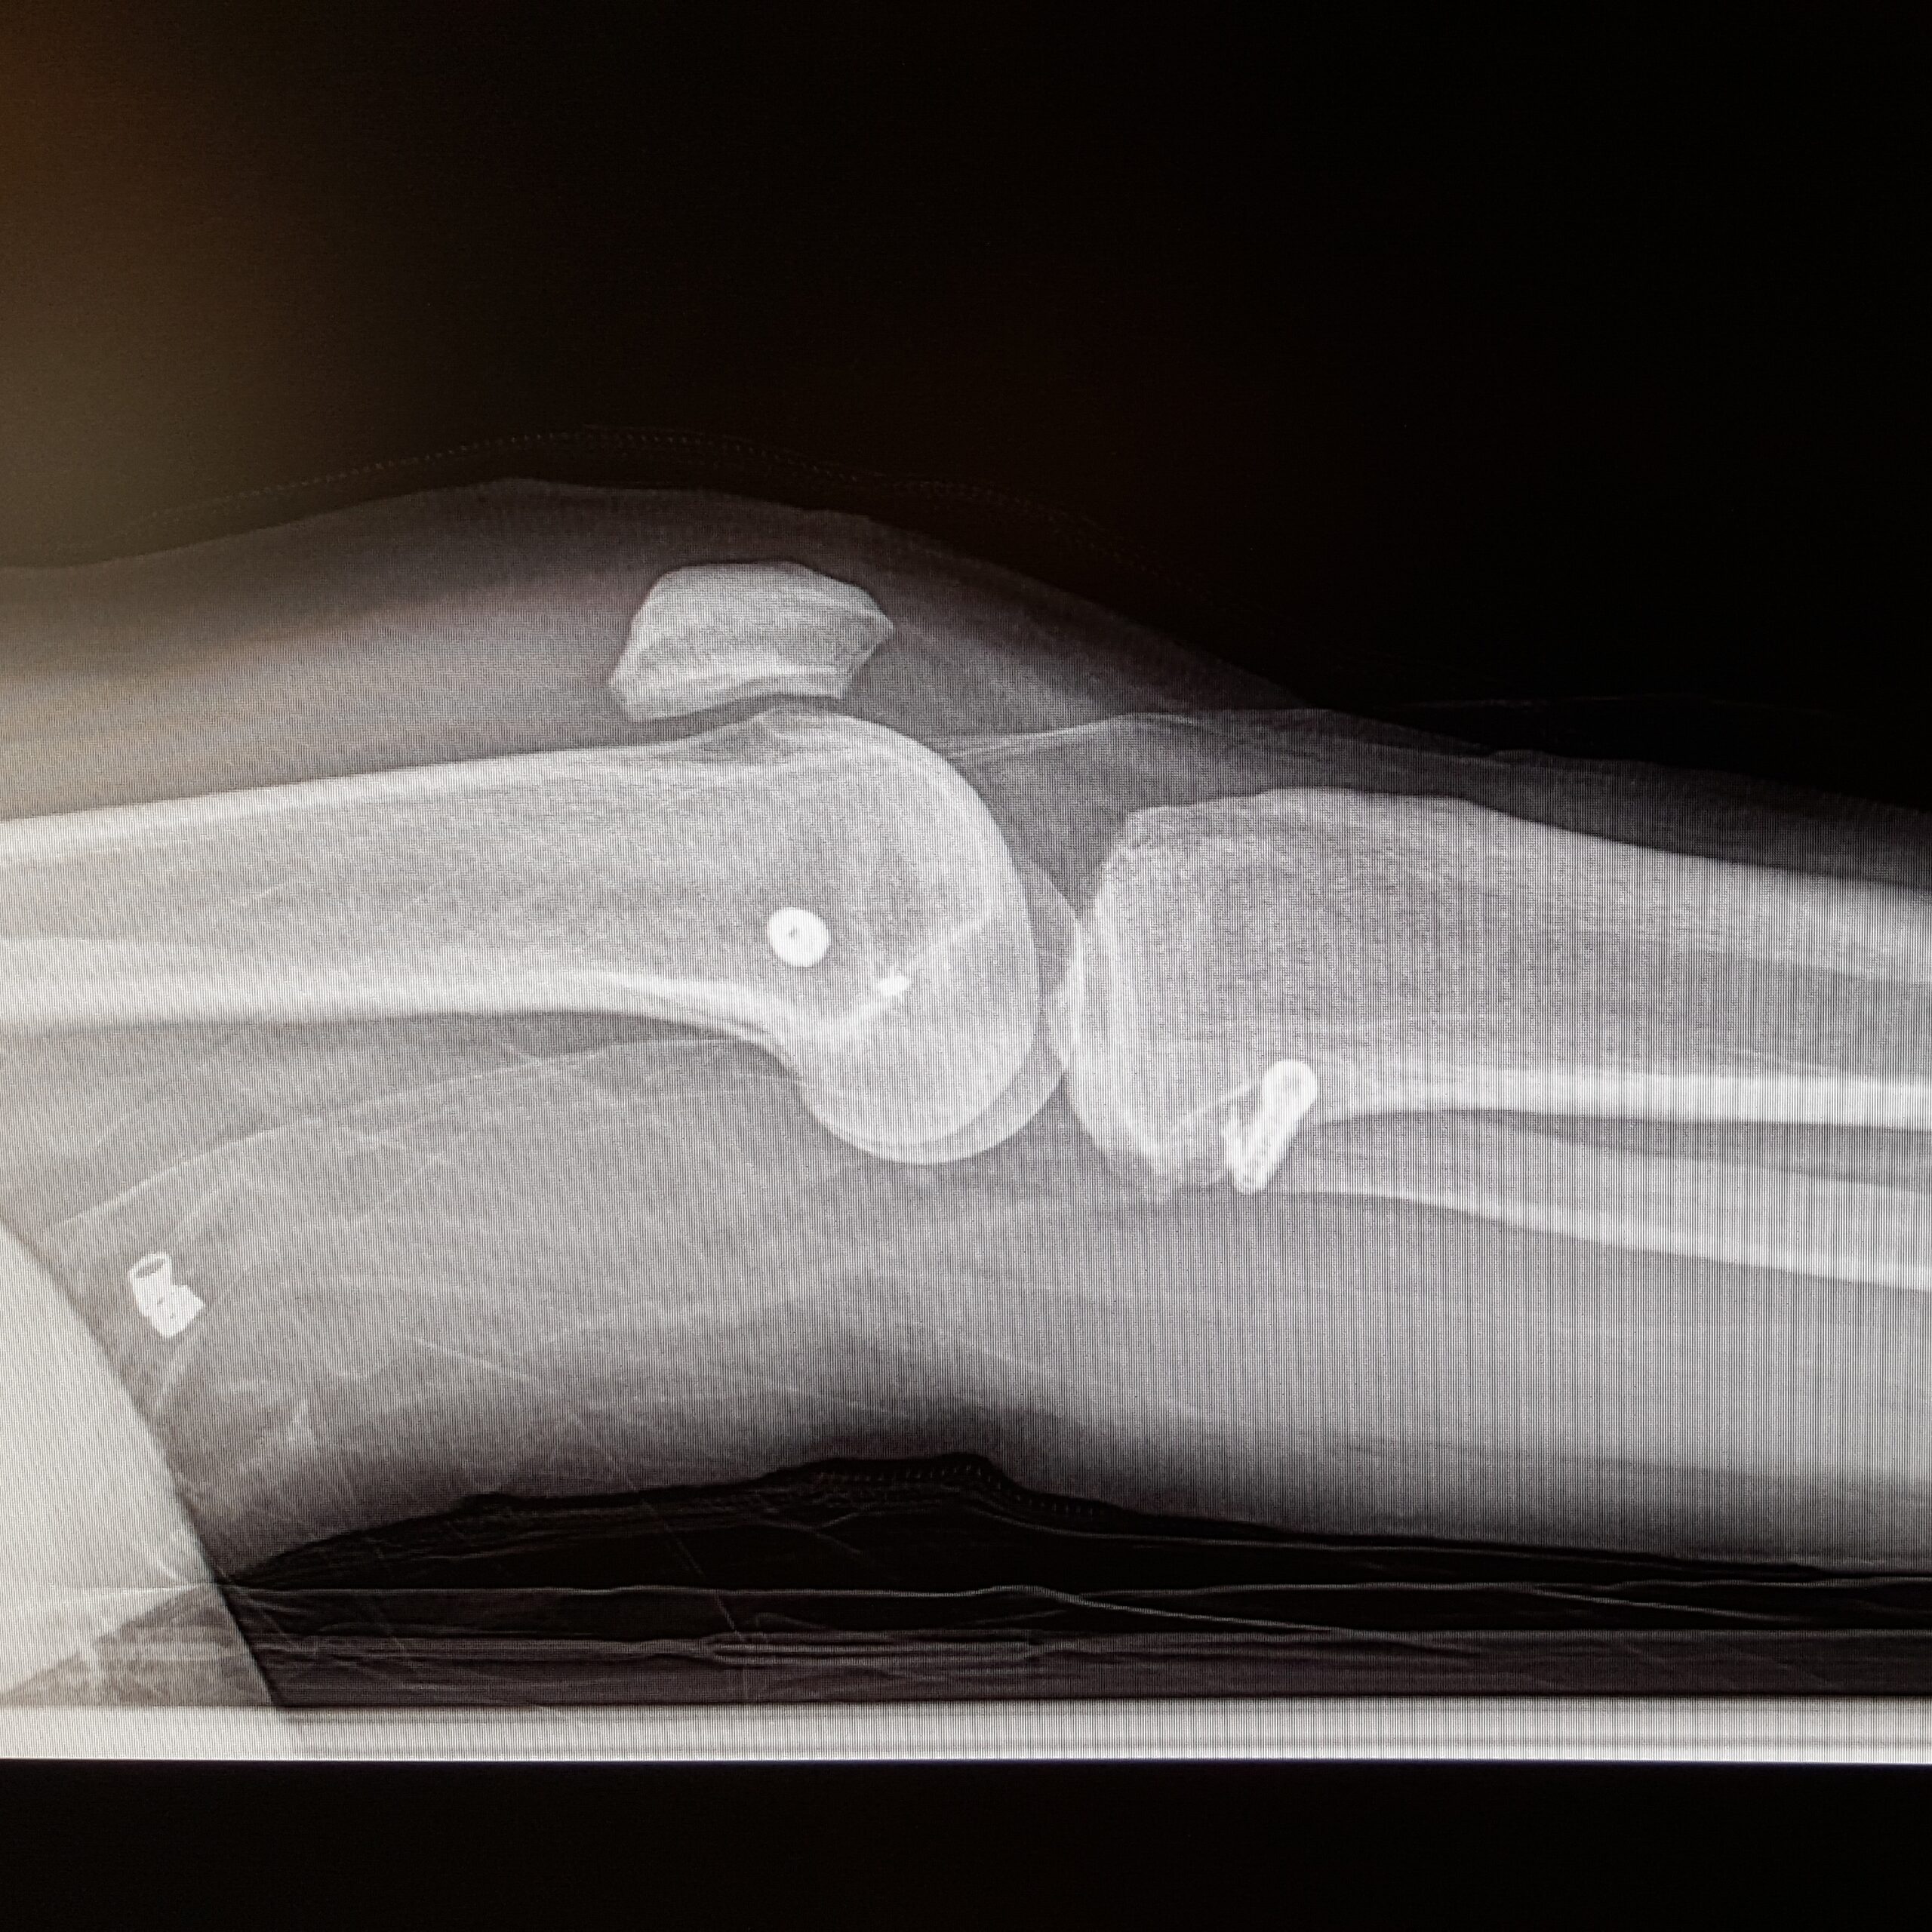

They then wheeled me over to the xray room and took a couple of xrays. You can clearly see the screws in my leg where they were grafting and fixing the fracture which is fascinating. I asked if this meant I would be stopped at airport security. They replied that it depends on the material they used in surgery but likely not. I thought darn, I’m already picked a lot for extra security, it would be nice to have a built in excuse. Oh, well.